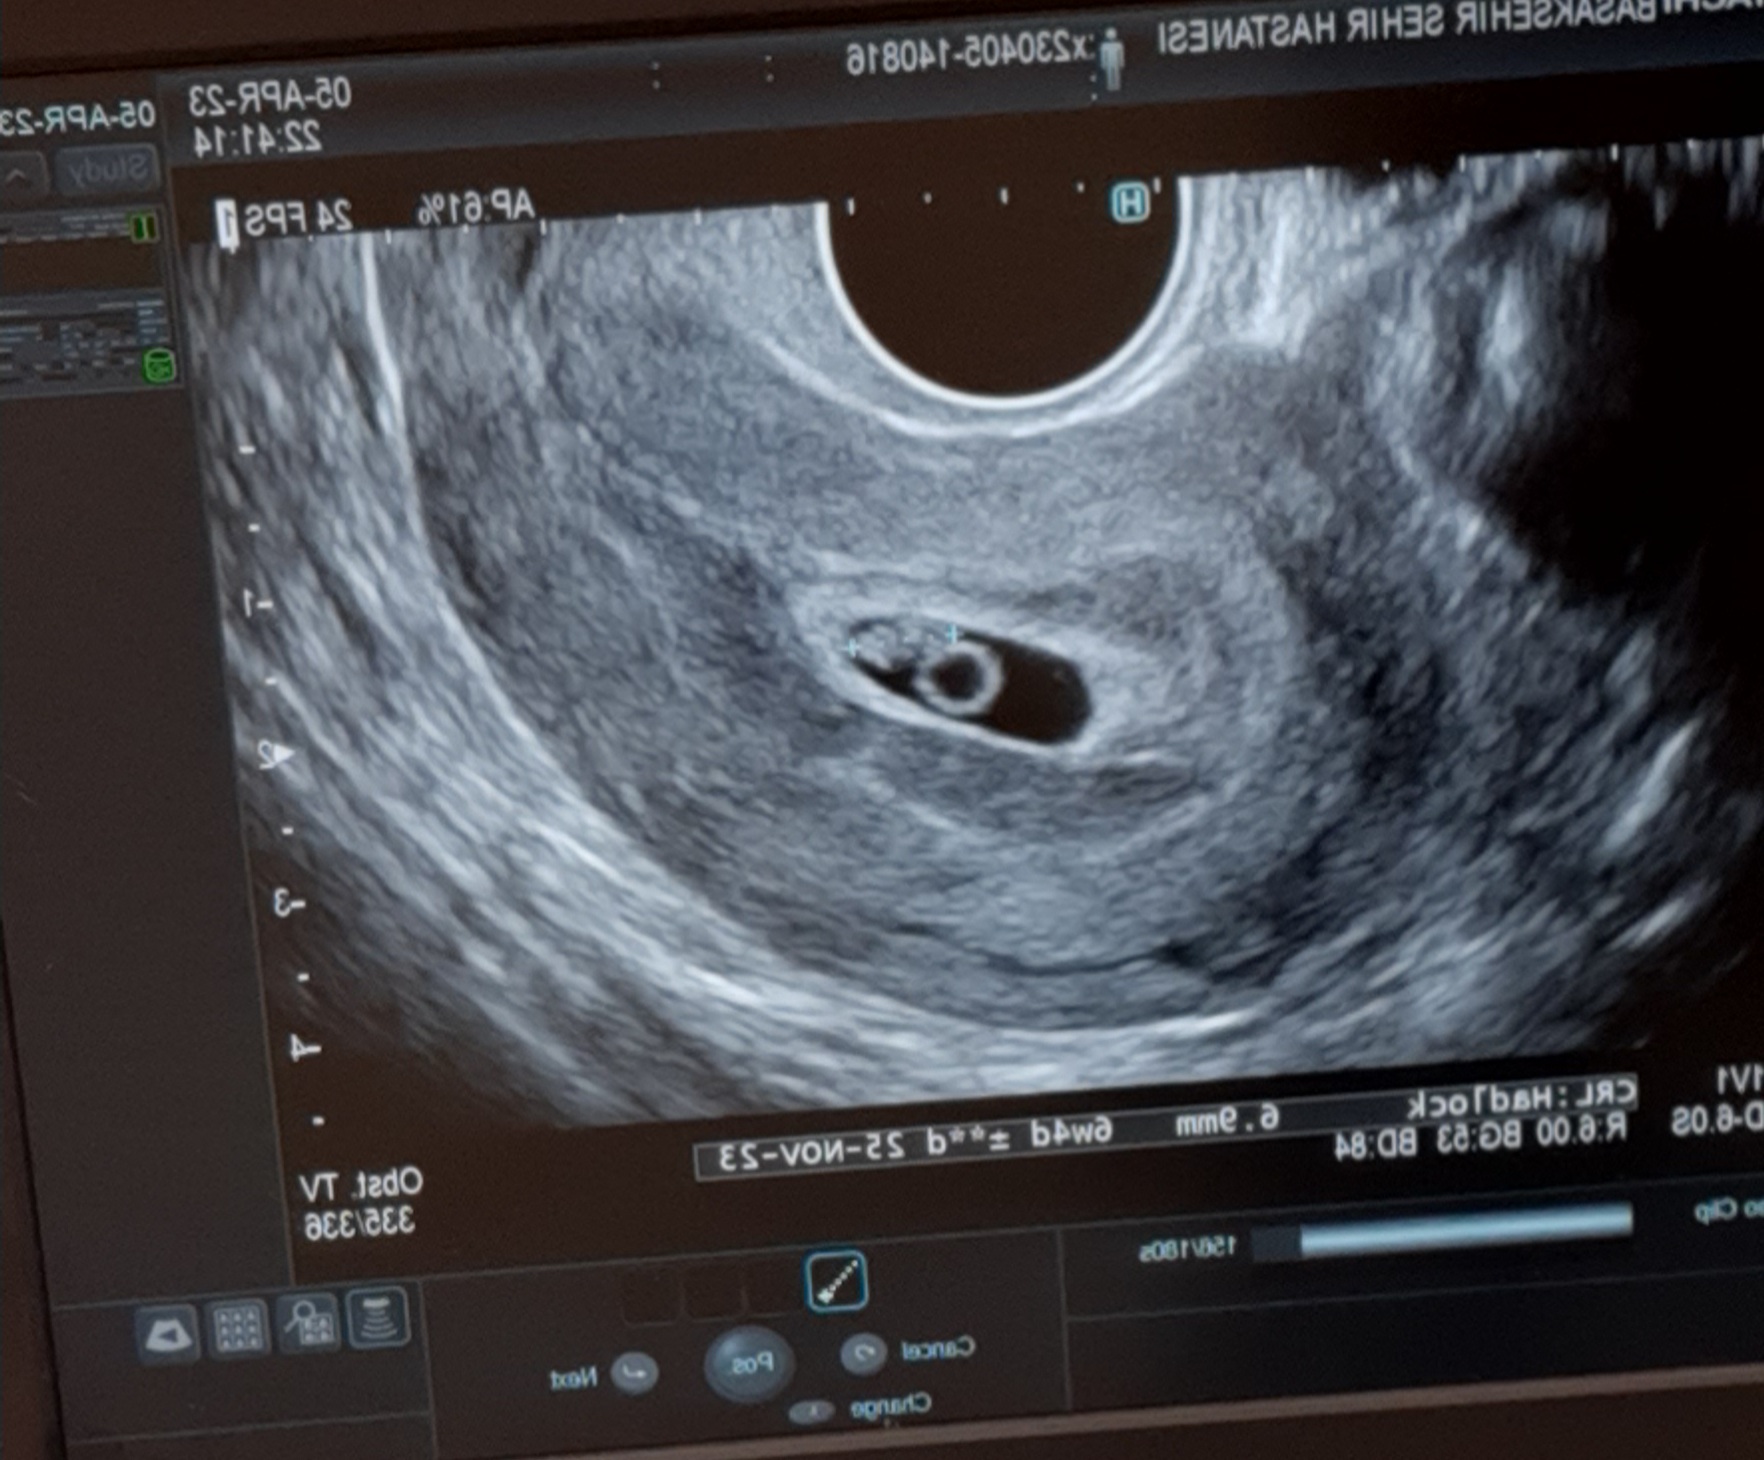

Kızlar gittim progestanı 2 katına çıkardılar kanama devam ederse hemen geri gel dedi doktor çok şükür bebeğim iyi ♥️ Bu da Minik Bebeğimin ilk resmi🥰

20230405_222927.jpg